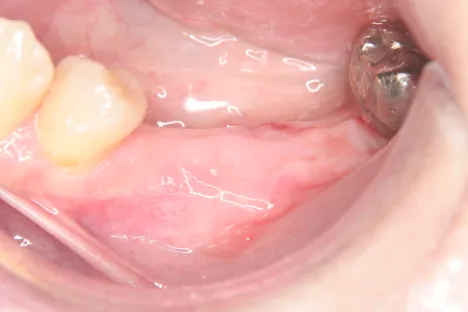

Dr.-Taniguchi_Fig.5

Fig. 5. Before secondary surgery 4 months later: No evidence of delayed healing, recession or infection of the mucous membrane.